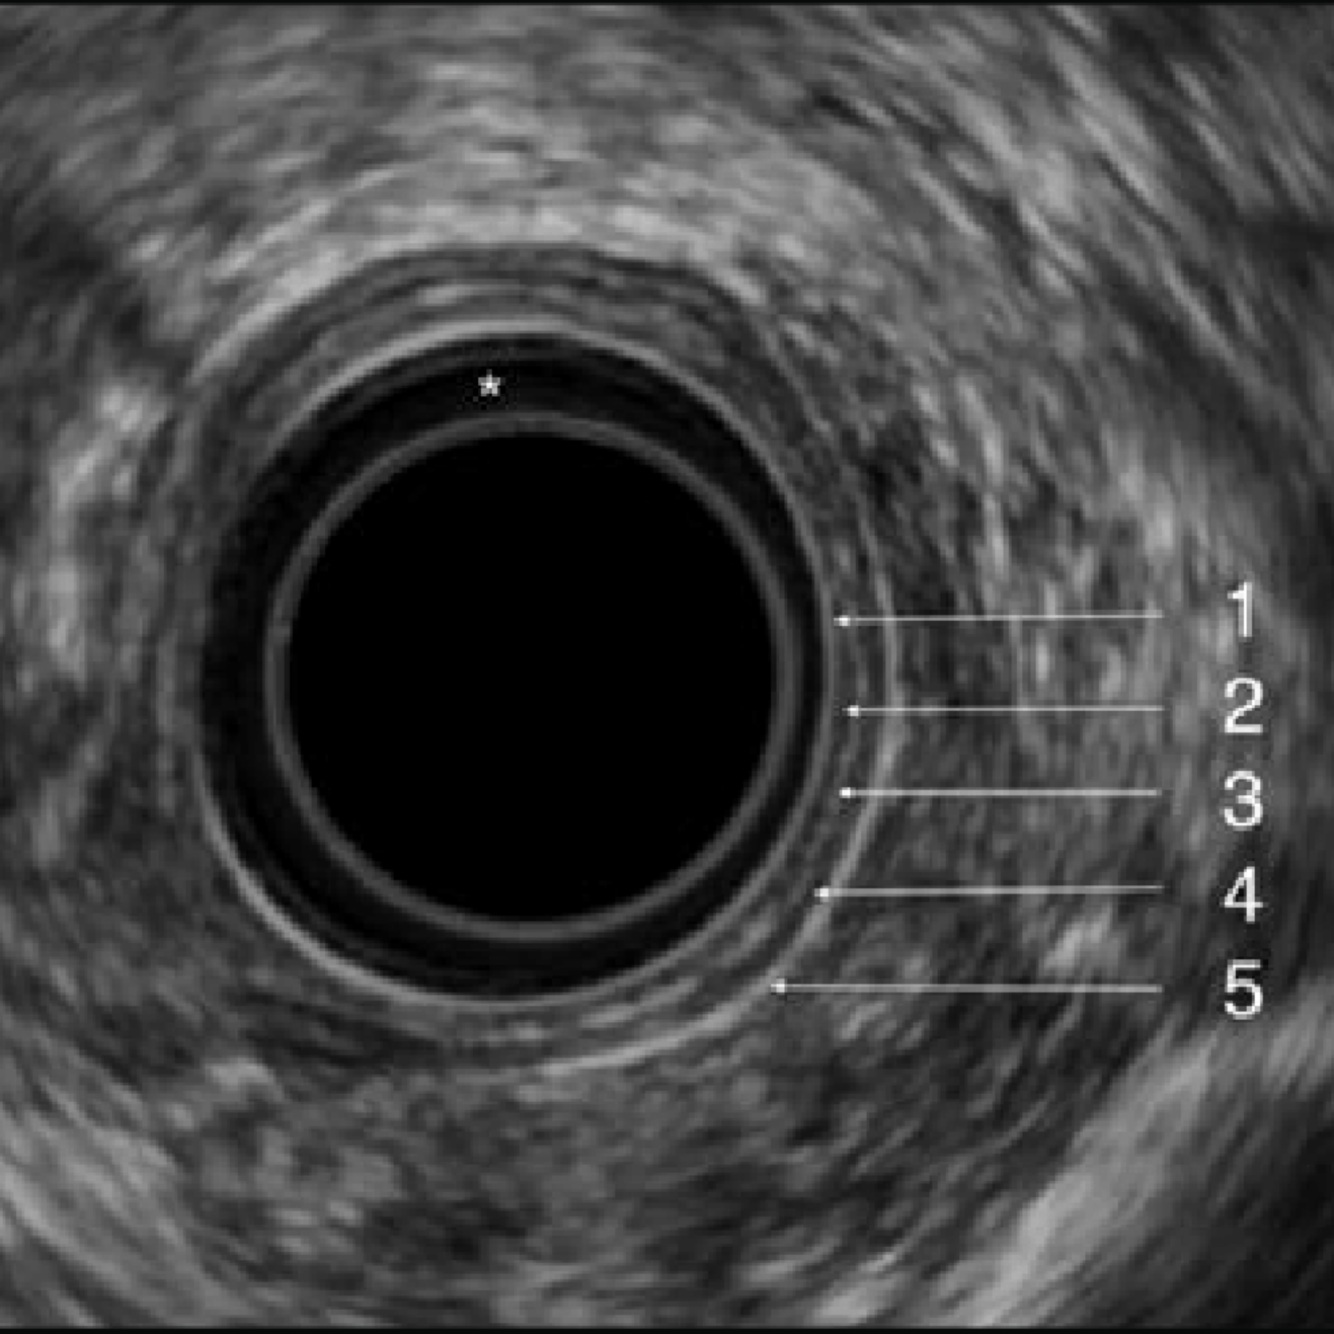

Layers seen on esophageal EUS

1st (hyperechoic) - epithelium/lamina propria

2nd (hypoechoic) - muscularis mucosa

3rd (hyperechoic) - submucosa

4th (hypoechoic) - muscularis propria

5th (hyperechoic) - paraesophageal tissue/adventitia

Muscle = dark (hypoechoic)